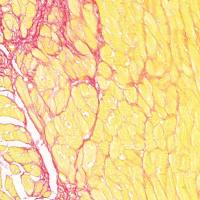

实验结果

贴壁细胞透射电镜